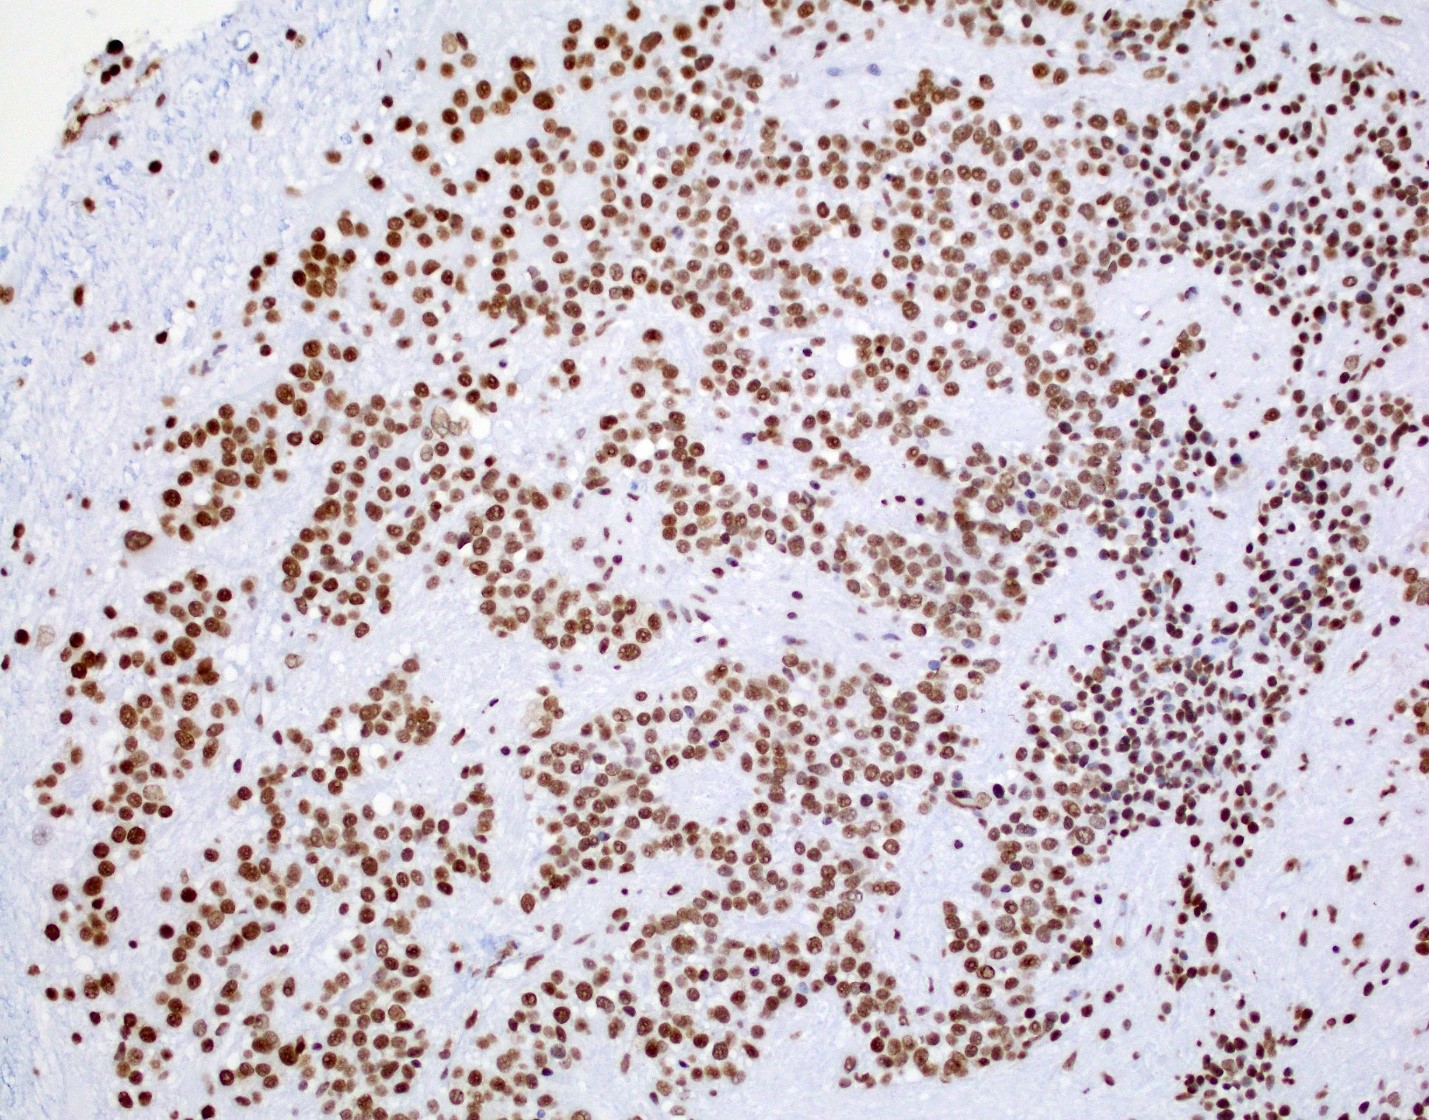

Positive stains

- Positive for S100, GFAP, vimentin

- Perinuclear dot-like pattern of EMA and D2-40 staining

- CD56 staining in lumina and tumor cells

- Variable membranous or dot-like staining for CD99

- Can have focal staining for keratin (CAM 5.2) and synaptophysin

- L1CAM can be positive in some supratentorial ependymomas but mostly is seen in RELA fusion tumors (Am J Surg Pathol 2019;43:56)

- In posterior fossa ependymomas, decreased expression of H3K27me3 is seen in posterior fossa group A, which has a worse prognosis (Acta Neuropathol 2017;134:705)